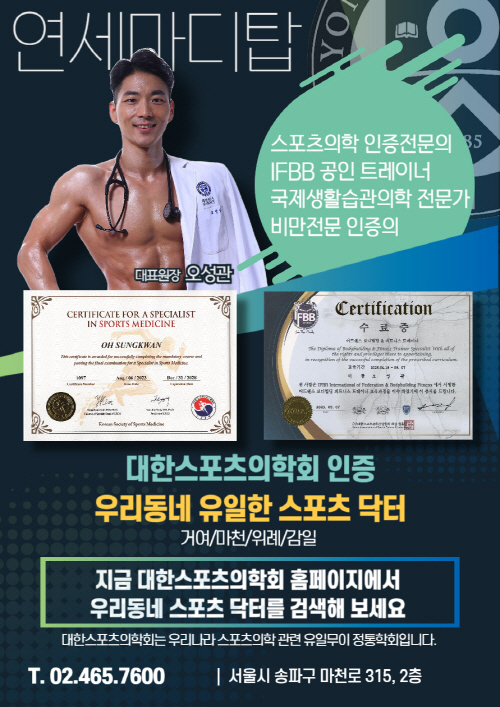

관절클리닉

관절클리닉

어깨통증, 무릎통증, 팔꿈치통증, 수부질환, 족부질환

비수술치료 클리닉

비수술치료 클리닉

도수/물리치료, 운동치료, 수액클리닉

척추클리닉

척추클리닉

목통증, 허리통증

비만통증클리닉

비만통증클리닉

체형 진단 및 운동치료

족부클리닉

족부클리닉

맞춤형 발진단 및 깔창제작